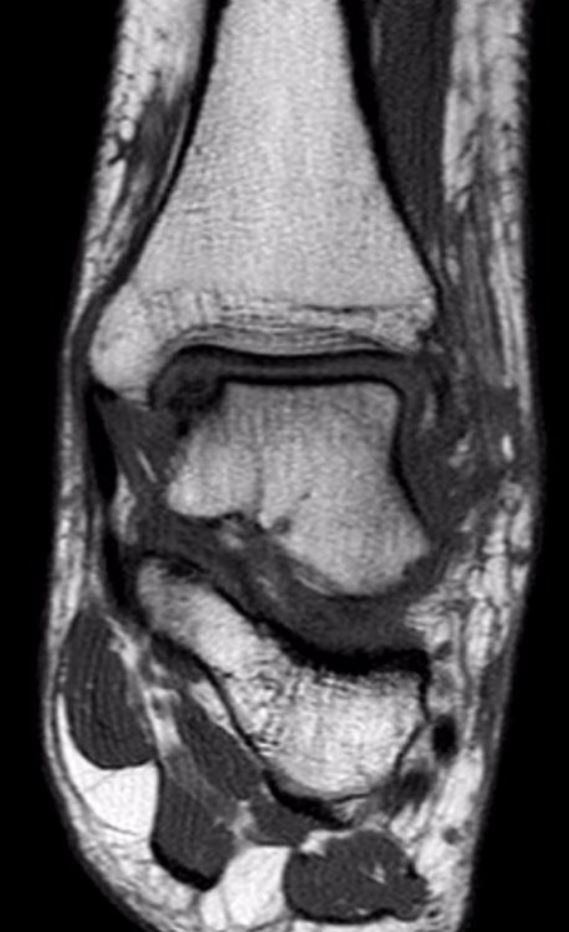

Difetto cartilagineo o difetto ostocondrale

Si tratta di aree localizzate con cartilagine e osso subcondrale (la porzione ossea al di sotto della cartilagine) danneggiate nell'articolazione della caviglia. I difetti osteocondrali sono di solito causati da lesioni alla caviglia, quali fratture e distorsioni. I sintomi più comuni includono dolore alla caviglia e gonfiore. I pazienti spesso lamentano blocchi e scricchiolii nella caviglia. La diagnosi viene realizzata utilizzando radiografie e risonanza magnetica. La TAC può essere utilizzata per valutare meglio eventuali lesioni che si approfondiscono nella porzione ossea. Il trattamento si basa sulla dimensione, posizione e stabilità del difetto osteocondrale. Solitamente la chirurgia consiste nell’asportazione della cartilagine danneggiata e nelle microperforazioni dell'osso nella sede di lesione per favorire la guarigione. Negli ultimi anni, si sono sviluppati substrati cartilaginei e scaffold artificiali che permettono la ricolonizzazione della cartilagine nella sede della lesione, dopo la sua bonifica.